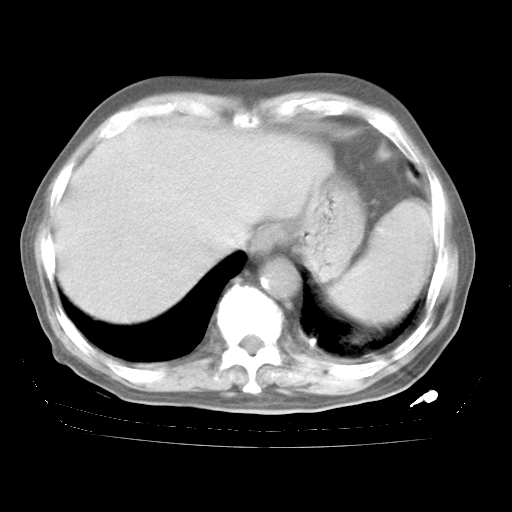

4月28日肺部CT——再次出现类似去年5月9日——透光度降低,“间质性”改变。

4月28日肺部CT——再次出现类似去年5月9日——磨玻璃样、间有“粟粒样”改变。

个人阅读4.14日肺部CT平扫:纵隔窗无异常,但肺窗示:双下肺内、后基底段有片絮状侵润影,部位以后基底段为著,以间质改变为主,呈急性肺泡炎征像,和首次住院影像学有相似之处。仅是个人读片,明日请相关专家再读片哈。其它建议同上。